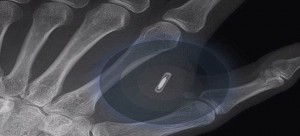

TG1: Inizia la campagna pubblicitaria per il chip sotto pelle

Ci vogliono semplificare la vita! Iniziamo col dire che Vox è sempre scettico sulle tesi complottiste, ciò non significa che a volte siano vere. E la questione dei chip sotto pelle, che abbiamo sempre ritenuto una tesi di individui strampalati (soprattutto per come veniva presentata, e forse era voluto dalla dis-informazione che si insinua in … Leggi tutto TG1: Inizia la campagna pubblicitaria per il chip sotto pelle